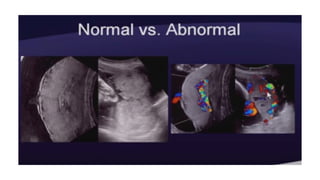

• DIAGNOSIS

Ultrasonography should be done by a competent in

cases of suspected placenta accrete.

Sensitivity of ultrasound imaging around 90% with

negative predictive values ranging between 95%

and 98%

Grey scale signs Colour Doppler Signs

Loss of retroplacental

hypoechoic zone

Dilated vascular

channels with diffuse

lacunar flow

Progressive thinning of

the retroplacental

(myometrium) < 2mm

Irregular vascular lakes

with focal lacunar flow

Multiple placental lakes Hypervascularity linking

placenta to bladder

Thinning of the uterine

serosa- bladder wall

complex (percreta)

Dilated, vascular

channels with pulsatile

venous flow over cervix

Elevation of tissue

beyond the uterine

serosa- extension of the

placenta beyond the

myometrium (percreta)

Poor vascularity at sites

of loss hypoechoic zone